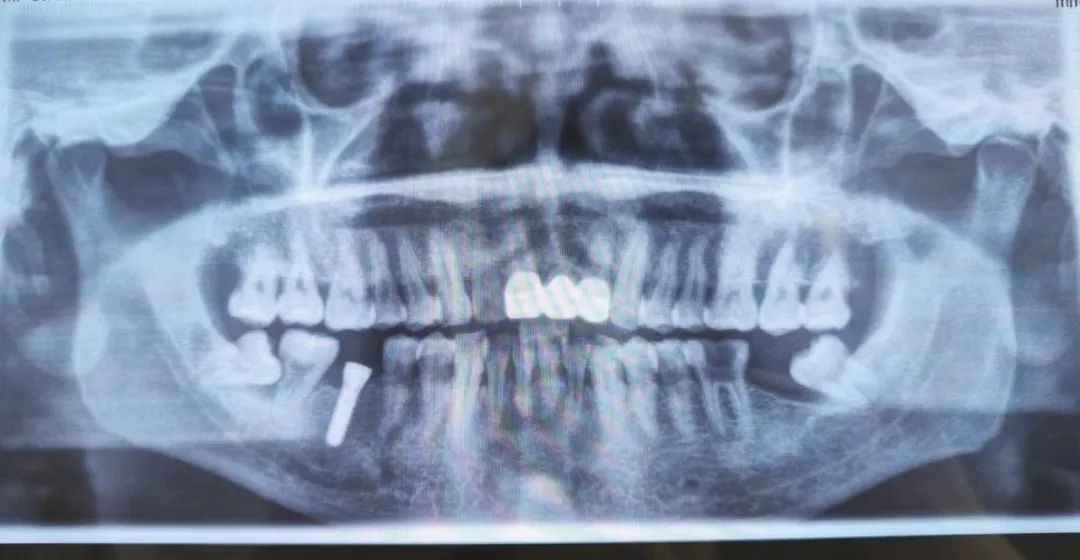

本次手术由李国光副主任医师和方明医生共同完成,是该中心首例种植牙手术。手术历时约30分钟,术中微创操作,患者全程无痛,术后无不良反应,整个诊疗过程舒适、安全、精准。经术后检查种植体位置精确。

种植体位置精确